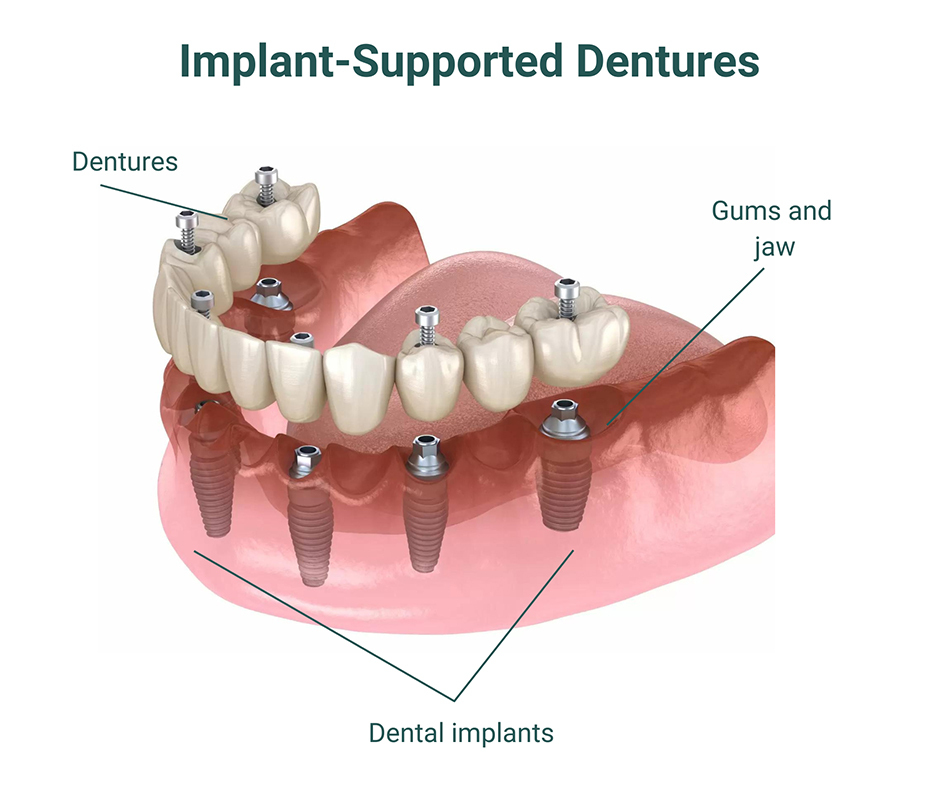

Traditional dentures can feel loose or uncomfortable during everyday activities. Implant-supported dentures attach securely to implants, offering better stability and confidence.

This option improves speech, makes eating easier, and reduces irritation. Implant dentures also help maintain facial structure by limiting ongoing bone loss.

All-on-X complete arch treatment is intended for patients who are missing most or all teeth within a single dental arch. A complete set of teeth is supported using a strategic number of implants placed in the jaw.

This fixed solution restores appearance and functionality while providing reliable, long-term support. Many patients appreciate the secure feel and simplified care.